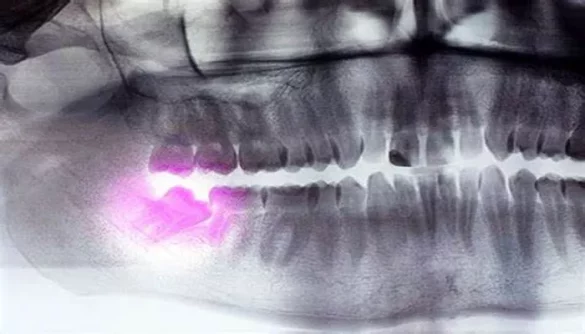

These teeth break through the gums in their intended position, without any obstruction or crowding. In contrast, impacted wisdom teeth are those that are unable to fully emerge due to a lack of space or an abnormal angle, causing them to become trapped beneath the gum line. Impacted wisdom teeth often lead to pain, infection, and other oral health complications.

Wisdom teeth, also known as third molars, are the last set of teeth at the back of the mouth that typically appear in early adulthood, usually between the ages of 17 and 25. While some people experience no discomfort from their wisdom teeth, others face significant pain, especially if the teeth become impacted or grow in improperly. But what about non-impacted wisdom teeth? Can they hurt even if they are not causing any obvious problems? This article will dive into the topic of non-impacted wisdom teeth, exploring whether they can cause pain, the reasons behind this pain, and what you can do about it.